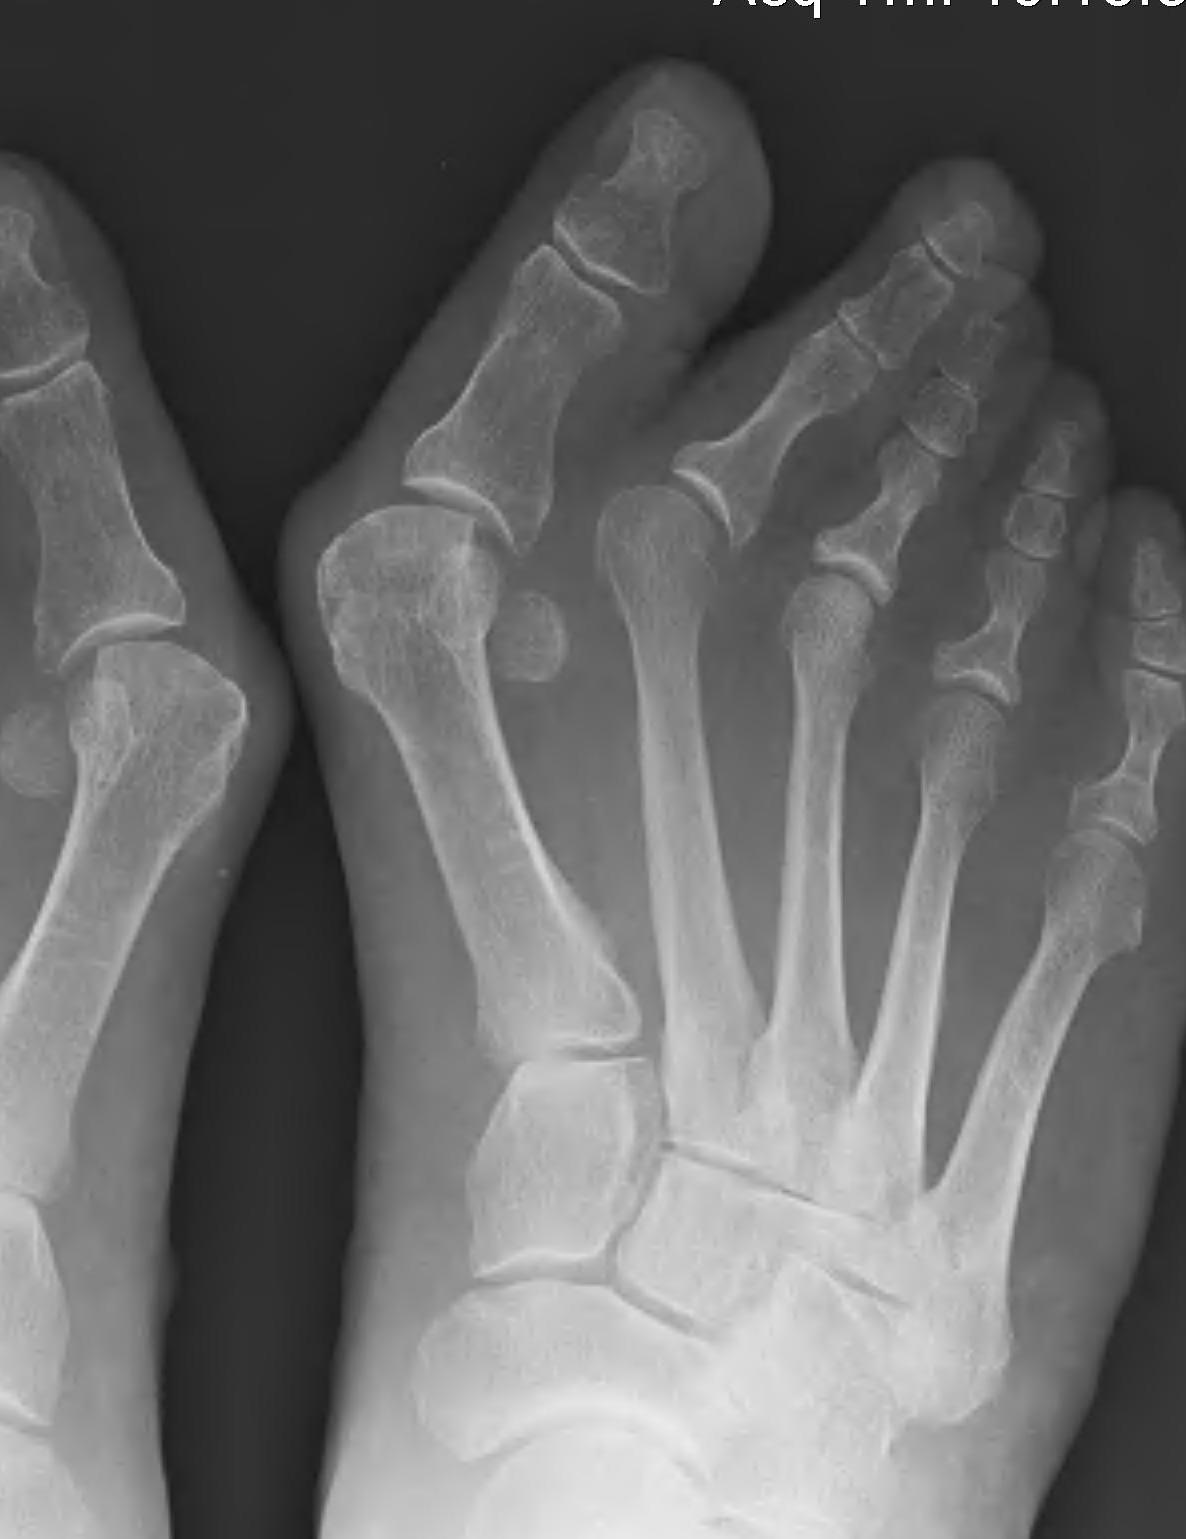

1. Correction of the hallux valgus and intermetarsal angles

2. Creation of a congruent MTP joint

3. Sesamoid realignment

4. Removal of the medial eminence

Arthrodesis

Indications

- hallux valgus with arthritis

- severe hallux valgus

- neuromuscular disease i.e. cerebral palsy

- rheumatoid arthritis

- salvage procedure for failed procedures